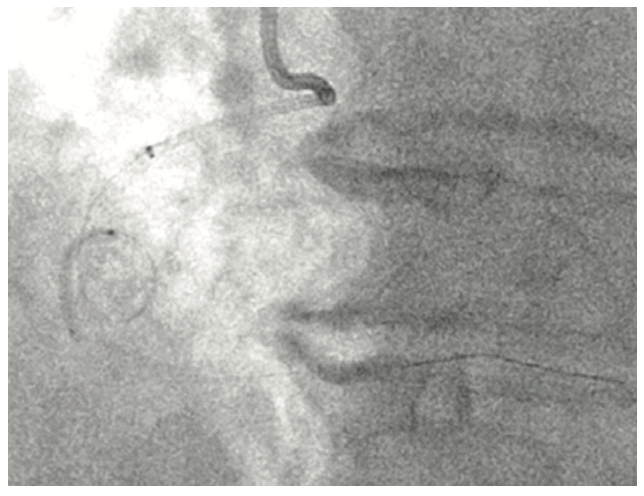

A 70-year-old gentleman presented with Canadian Cardiovascular Society (CCS) class III angina despite two anti-anginals (Metoprolol XL 25 mg daily and ranolazine 500 mg BID). His myocardial perfusion imaging demonstrated medium-sized inferior wall reversible defect with normal left ventricular function. His other comorbidities included chronic atrial fibrillation (on apixaban 5 mg BID), hypertension, and hyperlipidemia (on rosuvastatin 40 mg daily). His angiography revealed severe stenosis of the mid right coronary artery (RCA) involving a 360-degree loop. Further analysis of the angiogram revealed multiple contiguous lesions in the RCA with severe calcific lesions proximal and distal to the loop (Figures 1 and 2). Given severe tortuosity, rotational atherectomy would be challenging and we were hoping to achieve a good result using a balloon catheter strategy.